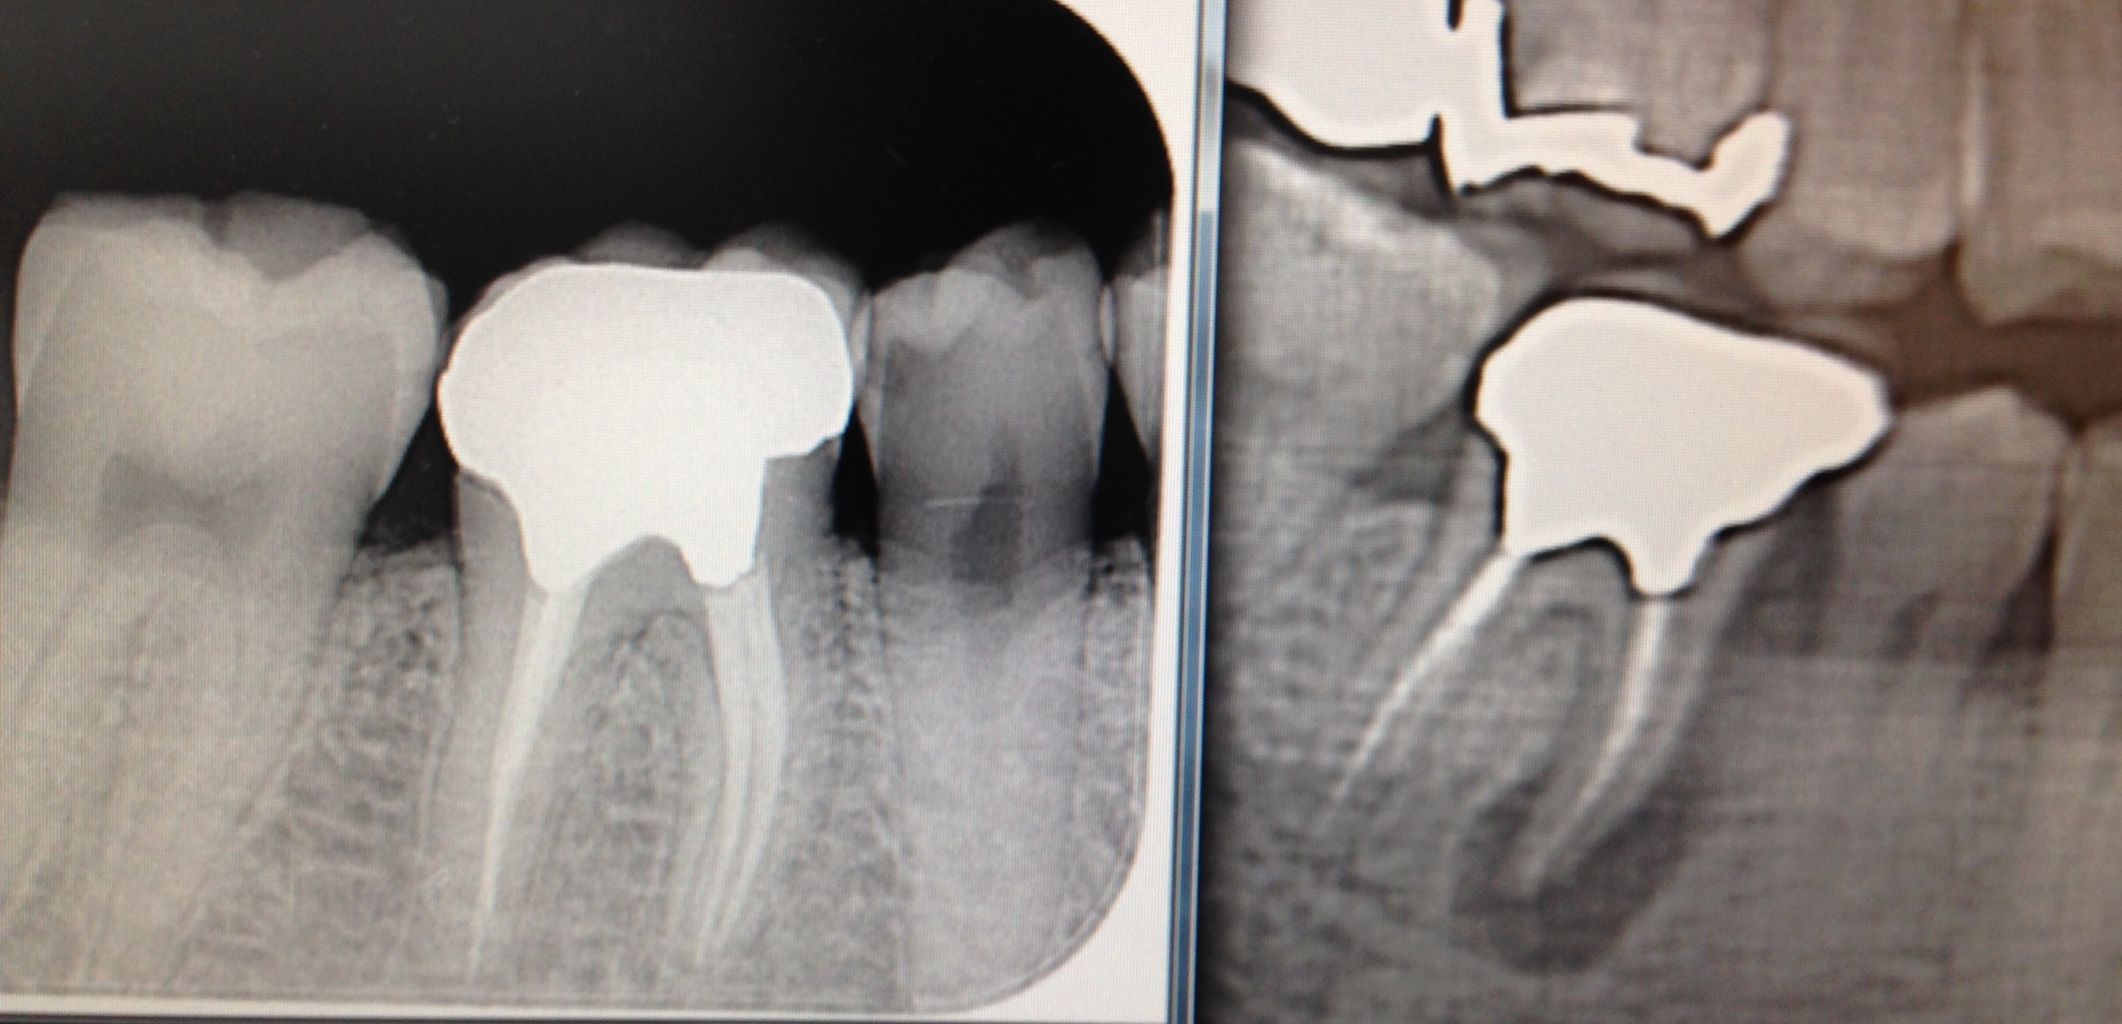

レントゲンで根の先が黒くなり、

膿んで骨がとけて、

ここに穴が開いてますね!

こんなに大きな穴でも、治ります。

少し根っ子を削るので、短くはなりますが。